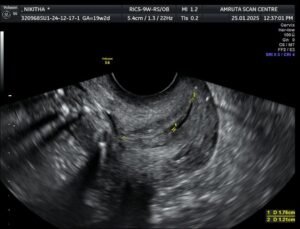

9. What is a cervix check scan?

A cervical status check evaluates the condition of your cervix, focusing on its length and whether it is open or closed

10. Why is a cervical check scan important?

Your cervix plays a key role in pregnancy. If it shortens or begins to open prematurely, it could signal a risk for abortion or preterm labour. If detected earlier appropriate therapy like bedrest and cervical stitch or cervical cerclage will be advocated with view to ensuring a healthy pregnancy outcome.

11. When is this scan recommended?

A cervical check is typically done in mid-pregnancy or if you’re having abdominal pain  or backache. Women with a history of previous preterm births or late abortions or previous cervical cerclage may require this scan.

12. When is this cervical check scan done.

Transvaginal Ultrasonography is the most accurate method for measuring cervical length. A small part of the probe is inserted into the vagina after it is covered with a condom to capture detailed images of the cervix.